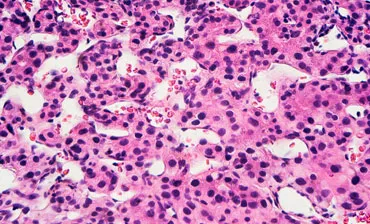

Hepatitis E is an acute or chronic infection with the hepatitis E virus (HEV). In Europe, most of the infections are locally-acquired and asymptomatic. Acute infections cause a self-limiting hepatitis, but can become chronic in immuno-compromised patients with the risk of the development of severe liver cirrhosis. HEV has also been described related to other clinical syndromes e.g. neurological.